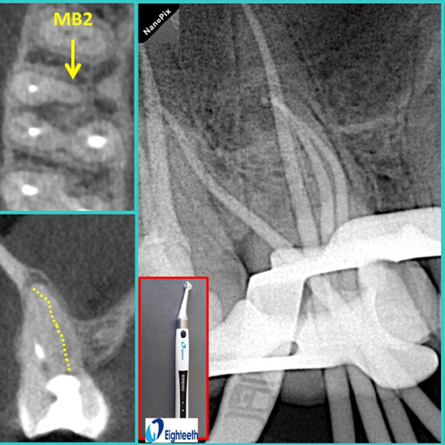

• 根管修復(fù)

• X射線(xiàn)診斷

產(chǎn)品評(píng)價(jià)和臨床案例

八顆牙用戶(hù)使用心得交流分享